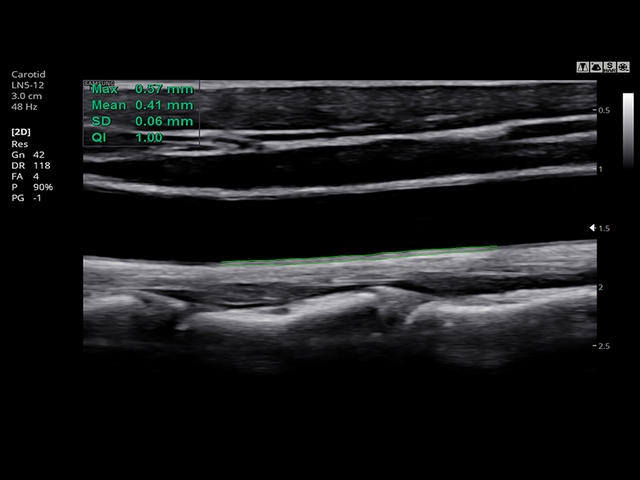

- Модуль Auto IMT - автоматическое вычисление комплекса интима-медиа общей сонной артерии (Intima Media Thickness). Данная оценка имеет большое значение для ранней диагностики атеросклероза и оценки риска развития инсульта и инфаркта миокарда.

Сонные артерии: автоматическая, полуавтоматическая, ручная трассировка доплеровского спектра; ПСС, КДС, %СтПлощ, %Ст Диам, площадь сосуда, диаметр сосуда, средняя толщина интимы, объемный кровоток.